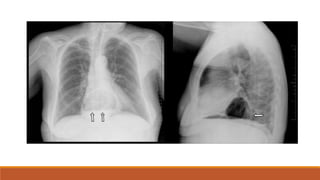

o Radiología

• Radiografía: Liquido blanquecino (Bario) que recubre el tracto digestivo para

ver el contorno del esófago, estomago e inicio del intestino.

• Tomografía: No es un procedimiento estándar

Diagnostico o Historia clínica oEndoscopia de vías digestivas altas: si hay síntomas de la enfermedad o signos de alarma o Radiología • Radiografía: Liquido blanquecino (Bario) que recubre el tracto digestivo para ver el contorno del esófago, estomago e inicio del intestino. • Tomografía: No es un procedimiento estándar